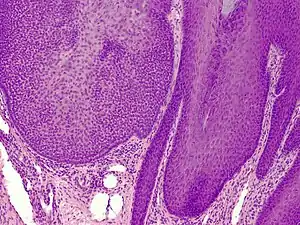

Trichilemmoma

Trichilemmoma (also known as "tricholemmoma"[1]) is a benign cutaneous neoplasm that shows differentiation toward cells of the outer root sheath.[2]:673[3] The lesion is often seen in the face and neck region. Multifocal occurrence is associated with Cowden syndrome, in which hamartomatous intestinal polyposis is seen in conjunction with multiple tricholemmoma lesions.

A trichilemmoma on a forehead